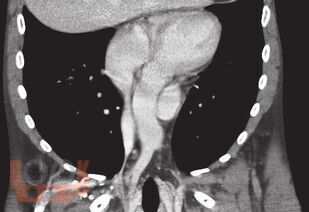

В книге представлены современные методы обеспечения сосудистого доступа у различных категорий пациентов с заболеваниями системы крови. Обсуждаются проблемы катетеризации вен как с учетом различных типов катетеров, так и особенностей течения заболеваний системы крови и проводимого лечения. Рассматриваются безопасные показатели для катетеризации при тромбоцитопении, врожденной и приобретенной коагулопатиях, тромбофилии, нейтропении, а также предпочтительные сосудистые доступы и типы катетеров для проведения противоопухолевой химиотерапии, трансплантации гемопоэтических стволовых клеток, заместительной терапии факторами свертывания крови, заместительной почечной терапии. Большое внимание уделяется осложнениям катетеризации, их профилактике и лечению. Книга содержит иллюстрации, которые демонстрируют различные аспекты рассматриваемых проблем. Представлен алгоритм по выбору типа катетера и сосудистого доступа у пациентов с заболеваниями системы крови. Рекомендуется гематологам, онкологам, анестезиологам-реаниматологам и медицинским работникам других специальностей, сталкивающимся в своей работе с обеспечением сосудистого доступа.